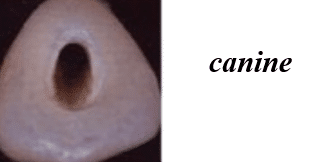

Shapes of the access cavity of all teeth

| Tooth | Access cavity shape | Average depth |

|---|---|---|

| Maxillary incisors | Triangular or oval (placed over the palatal surface) |

3-4 mm |

| Mandibular incisors | Triangular (placed over the lingual surface)

|

3-4 mm |

| Maxillary canines | Oval (placed over the palatal surface)

|

4-5 mm |

| Mandibular canines | Oval (placed over the lingual surface)

|

4-5 mm |

| Maxillary premolars | Oval or rounded (located over central part of the tooth)

|

4-5 mm |

| Mandibular premolars | Oval (over central of the tooth, slightly to the lingual)

|

4-5 mm |

| Maxillary molars | Trapezoidal (located over the mesial buccal cusp or the central part of the tooth)

|

5-6 mm |

| Mandibular molars | Trapezoidal or rhomboidal (centered over the mesial buccal cusp)

|

5-6 mm |

| Maxillary second molars | Trapezoidal (centered more mesially and palatally, slightly off-center) | 5-6 mm |

| Mandibular second molars | Trapezoidal or rhomboidal (centered over the mesial buccal cusp) | 5-6 mm |

| Maxillary third molars | Oval or trapezoidal | 5-7 mm |

| Mandibular third molars | Trapezoidal | 5-7 mm |